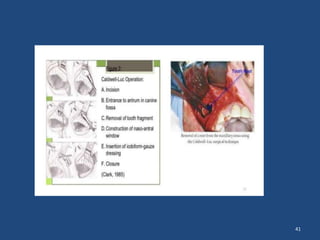

---Displacement the root to max sinus it can be

if it failed it will go to Claudelwelluc operation to open

the max sinus to remove the RR,

Displacement of the

root

- maxillary

antrum

41